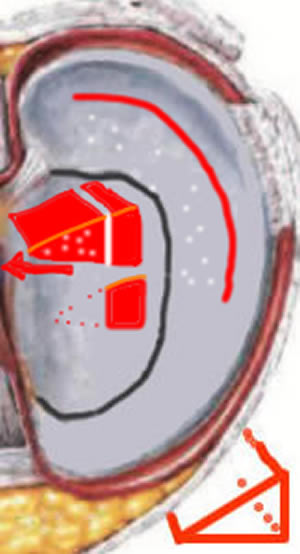

Anse de seau méniscale

Ici, la fissure est périphérique, transfixiante, instable, libérant un fragment, mais qui reste retenu à chaque extrémité (comme une anse de seau). Ce fragment est instable (comme la languette) : il peut bouger.

Blocage méniscal

Le fragment méniscal peut basculer comme "l'anse d'un seau" et bloquer le genou en empêchant l'extension complète.